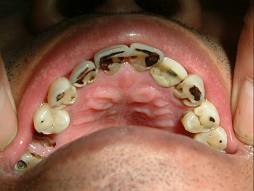

猛性龋是 ( ) A.短期内多数或全口牙发生急性龋 B.龋坏包括牙面广泛 C.唾液分泌减少 D.龋坏进展较快 E.以上全是

选项 A.短期内多数或全口牙发生急性龋 B.龋坏包括牙面广泛 C.唾液分泌减少 D.龋坏进展较快 E.以上全是

答案 E